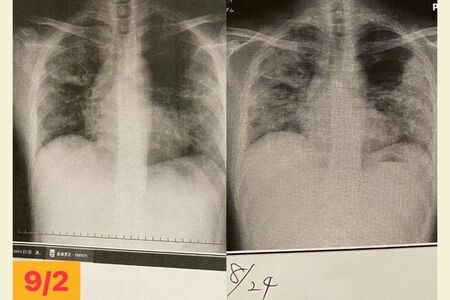

東京の医療崩壊をうかがい知ったのは、転院先で撮った肺のレントゲン写真だった。

「肺炎治療専門の先生が僕のレントゲン写真を見たとき、第一声が『東京はこの症状で退院させるの? 通常ではありえない』でした。東京では多くの命を助けるために、できるだけベッドを空けなければならない状況だったと思います。しかし、この状態での退院は、すでに『医療崩壊が起きている』と判断される状況だったようです」

「当初、転院先の病院では1日から2日の入院で終わる予定でした。しかし僕のレントゲン写真を確認した先生から、『退院するレベルではなく、1~2週間入院の必要がある』と説明を受けました」

治療にはステロイドの強めの薬が投与され、9月2日から6日でかなり良くなった。本来2週間の入院だったが、通院でも大丈夫だと診断され、9月7日に退院できた。